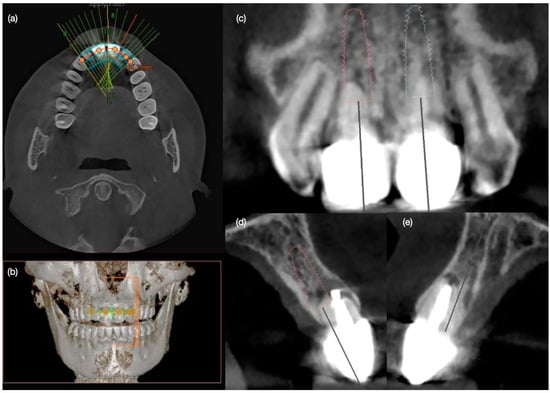

Figure 2. Radiographic evaluation of the central incisors with infection at the apical area. (a) CBCT occlusal view, and (b) frontal view; (c) frontal view and (d) and (e) lateral views of central incisors.

A 30-year-old female patient presented to the clinic with the chief complaint of having some exudated tissue appearing in the upper anterior area of her mouth, and also disliking her smile (Figure 1). Patient stated that she had previous dental care in another city, including endodontic treatment and crowns for both maxillary central incisors 5 years prior. The patient had undergone extraction of both maxillary first premolars followed by orthodontic treatment 10 years ago. After clinical, photographic, radiographic, and cone beam computed tomography (CBCT) evaluation, the maxillary incisors were diagnosed with chronic periapical abscesses. Other findings included incisal wear for the right canine, right lateral incisor, and left canine, and a stained old composite restoration on the incisal edge of the left lateral incisor. The patient noted that the wear was a significant esthetic concern. Moreover, both central incisors presented grade II mobility. Due to the chronic periapical abscess in both central incisors, the long metal posts, mobility, and apical resorption, the teeth were determined to be non-restorable, and extractions were recommended (Figure 2). The patient was offered different treatment options for the replacement of both central incisors, such as a fixed dental prosthesis from lateral incisor to lateral incisor, a removable partial dental prosthesis, and implant therapy. The patient was also offered minimally invasive porcelain veneers for all her teeth displayed while smiling, from the left first molar to the right first molar, based on her esthetic concerns of wear. Resin composite veneers were similarly offered, and compared and contrasted with porcelain veneers. The patient preferred to have implants, and accepted to have porcelain veneers for the remaining anterior teeth, in order to improve the entire smile. The patient was informed about the option of immediate implant therapy or two-staged implant surgery, and she opted for immediate implant therapy in order to decrease the number of surgical procedures.

Diagnostic three-dimensional digital scans (iTero Lumina, San Jose, CA, USA) of the maxilla and mandible were taken, and a traditional facebow record (Artex Facebow, Amann Girrbach, Koblach, Austria) was obtained. Printed models (Phrozen Sonic Mini 8K Resin 3D Printer, Phrozen Technology, Hsinchu City, Taiwan) were then fabricated and mounted on a semi-adjustable articulator (Artex CR, Amann Girrbach, Koblach, Austria). A diagnostic wax-up was performed and mounted in the articulator. The patient also received an intra-oral mock-up with a putty index guide (Elite P&P, Zhermack, Badia Polesine, Italy). An initial CBCT scan and the intra-oral scan were used to digitally plan the implant placement (Exocad DentalCAD, Darmstadt, Germany) and print the surgical guide (Phrozen Sonic Mini 8K Resin 3D Printer, Phrozen Technology, Hsinchu City, Taiwan) (Figure 3). Atraumatic tooth extractions were performed for both maxillary central incisors with the use of a periotome (Anterior Straight PT6, Hu-Friedy, Chicago, IL, USA) and forceps (Upper Anterior Atlas FAF1IS, Hu-Friedy, Chicago, IL, USA), only providing vertical forces, and avoiding any horizontal force (Figure 4). The extraction sockets were cleaned thoroughly with curettes (Universal Curette, Hu-Friedy, Chicago, IL, USA), and the abscess cavity was irrigated with saline solution and chlorohexidine to flush out all the debris and blood. The 3D-printed surgical guide was placed in position, osteotomies were performed, and two implants (3.5 mm diameter; 11.50 mm length, Helix GM, Neodent, Basel, Switzerland) were placed at the planned depth (Figure 5 and Figure 6). An autogenous soft tissue graft was harvested from the palate and positioned on the facial surface of the maxillary left side implant using polyethylene sutures. Interim abutments (Gm Temporary Abutments for Crown, Neodent, Basel, Switzerland) were placed with screw-retained non-occluding interim crowns (Figure 7). The patient had regular follow-up evaluations at 2, 4, 7, and 10 weeks, and at 3 and 4 months, after the implant placement. The provisional restoration was recontoured at week 10, and new sets of interim restorations were made at 3 and 4 months (Figure 8). The patient and clinicians were fully satisfied with the contour obtained with the last set of provisional restorations at 4 months, and it was decided to continue the final stage of the treatment (Figure 9).